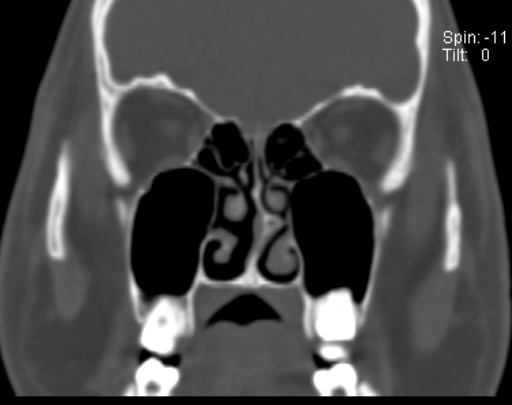

哪些患者适合行外科治疗呢?一,经规范化药物治疗和(或)免疫治疗,鼻塞和流涕等症状无改善,有明显体征,影响生活质量;二,鼻腔有明显的解剖学变异伴功能障碍,比如鼻甲肥大、鼻中隔偏曲。伴有鼻中隔偏曲的常年性过敏性鼻炎患者,采用鼻内镜下鼻中隔偏曲矫正手术,疗效显著。

外科治疗的手术种类有哪些呢?一是主要以改善鼻腔通气功能为目的的下鼻甲减容术、鼻中隔偏曲矫正术;二是以降低鼻黏膜高反应性为目的的选择性神经切断或阻断术。